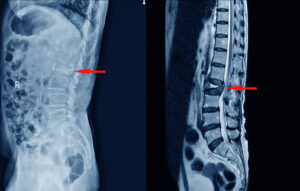

Understanding Degenerative Disc Disease

Degenerative disc disease involves the gradual wear and tear of the spinal discs, which is a normal part of aging. However, certain jobs that involve heavy lifting or repetitive twisting and turning can accelerate this process. Even sedentary jobs can contribute to the disease’s progression, as lack of regular physical activity can weaken back muscles, making them more susceptible to injury.